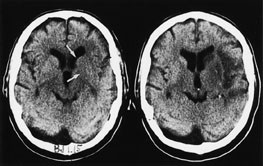

De følgende eksempler er hentet fra pasienter innlagt i Nevrologisk avdeling, Haukeland Sykehus, med akutt cerebral iskemi og undersøkt med CT innen tre timer og ti minutter etter symptomdebut (bildet til venstre, fig 1 – 4) og med oppfølgende CT (bildet til høyre, fig 1 – 4). Bildene illustrerer de forannevnte kardinaltegn (tab 1).

Hyperdens a. cerebri media-tegn (HACMtegn) (fig 1). HACM-tegn er strengt tatt ikke et tegn på tidlig infarkt, men er CT-tegn for okklusjon av a. cerebri media. Oftest er hovedstammen okkludert, med høy risiko for utvikling av et komplett mediainfarkt. Falskt positivt HACM-tegn kan forekomme ved arteriosklerose eller ved høy hematokrit. I begge tilfellene ville man forvente symmetriske forandringer, men skjev hodestilling under CT-undersøkelsen kan føre til et asymmetrisk bilde med tilsynelatende ensidig HACM-tegn.